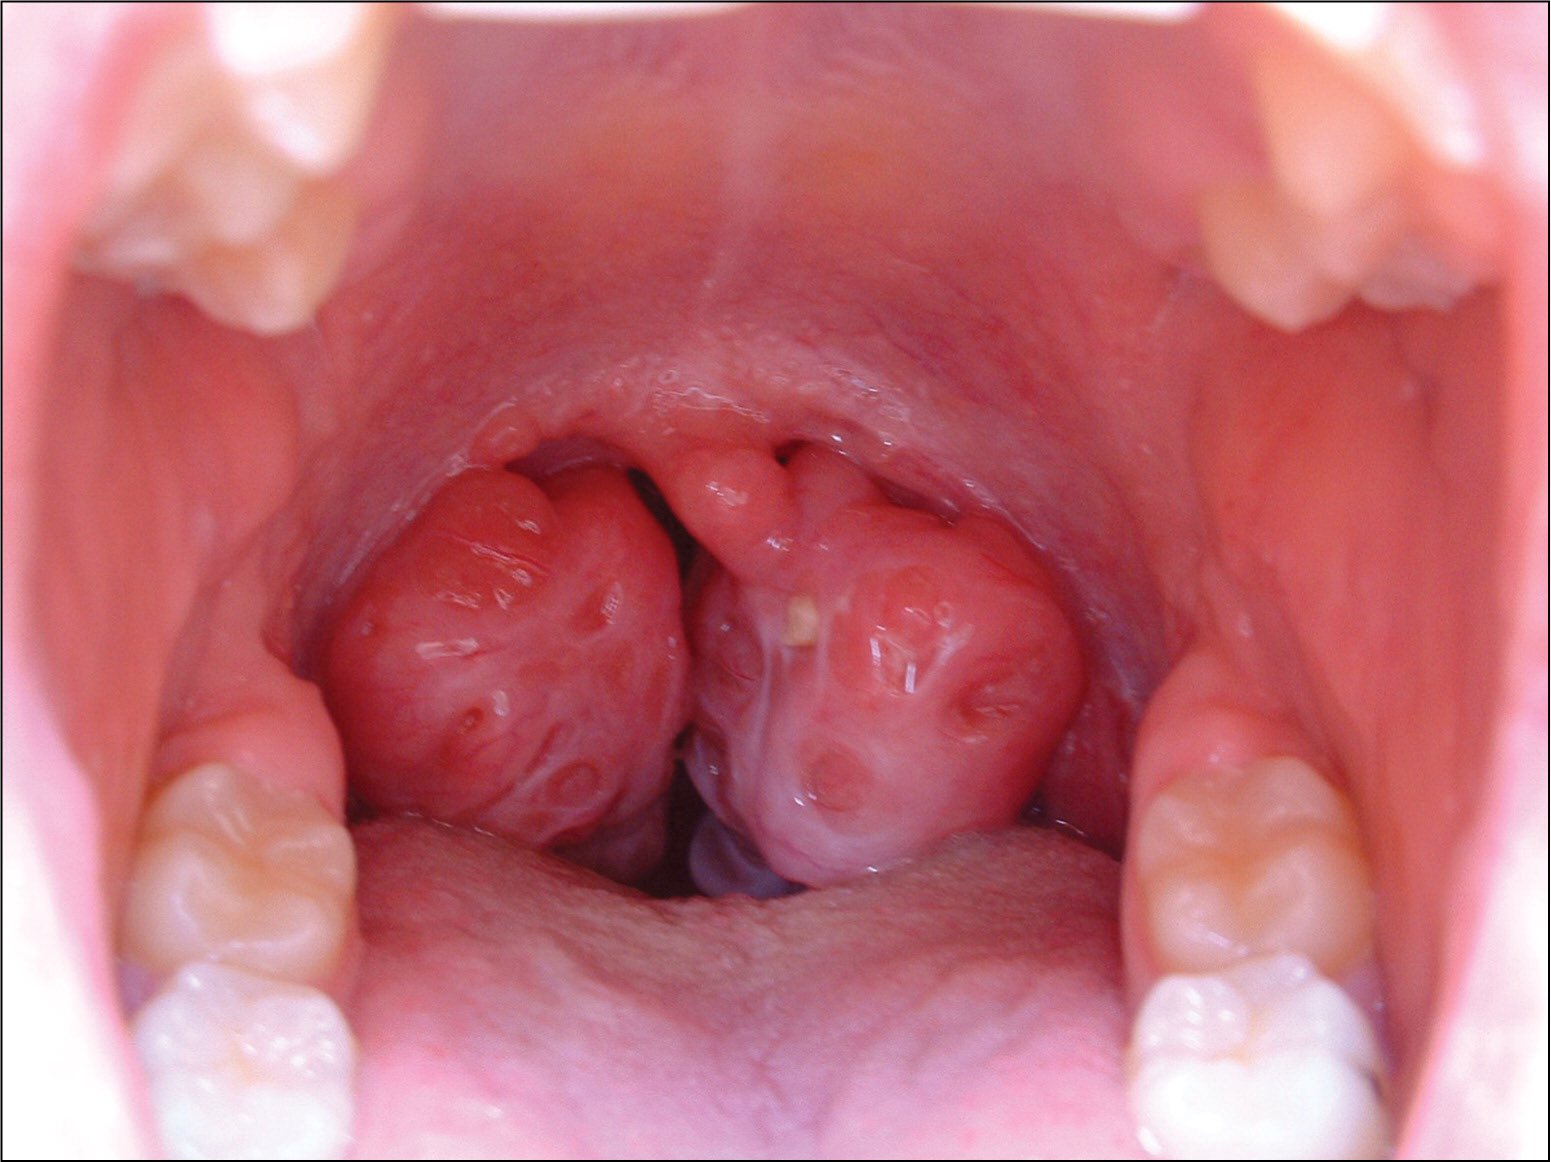

مضاعفات عملية اللوز واللحمية للاطفال. مضاعفات عملية اللوز واللحمية للاطفال نتحدث عنها اليوم بالتفصيل اللوز واللحمية من المشاكل الصحية التي تواجه الكثير من الأشخاص وبالتحديد الأطفال حيث يكونان درع واقي للجسم ويلعبان دور هام في الحماية من البكتريا. هذه الغدد عبارة عن جزء من الجهاز المناعي في الجسم حيث تقوم بالإمساك بالجراثيم المختلفة في الأنف قبل أن تسبب المرض لك. كيف أصبحت جراحة اللوز البسيطة التى ارتبطت لدى أطفال الثمانينيات والتسعينيات بالكثير من الآيس كريم جراحة قاتلة أحيان ا ما يفقد الأطفال حياتهم أثناء إجرائها إما بسبب خطأ فى إجراء الجراحة أو فى التخدير. 2 ظهور غشاء أبيض مكان العملية.

مضاعفات عملية اللوز واللحمية للاطفال 1 الشعور بألام شديدة بالأذن. مضاعفات لوز الحلق المتضخمة. لحمية الأنف عبارة عن غدد تتواجد في أعلى الحلق وخلف الأنف وفي سقف الفم. تشكل عملية استئصال.

تعرف على ما يجب فعله و نصائح بعد عملية اللوز واللحمية للاطفال عندما يقوم الطفل بإجراء عملية اللوز أو اللحمية فعلى من يقوم برعايته أن يتعرف على ما الذي يحدث بعد اجراء إستئصال اللوزتين واللحمية وغالبا ما يتم استئصال. مضاعفات عملية اللوز واللحمية للأطفال. عملية استئصال اللوزتين من العمليات المنتشرة للأطفال بسبب الإصابة بالتهابات اللوز المتكررة فلا تترددي في الذهاب إلى الطبيب في الوقت المناسب عند ظهور أعراض التهاب اللوزتين على طفلك لاتخاذ.